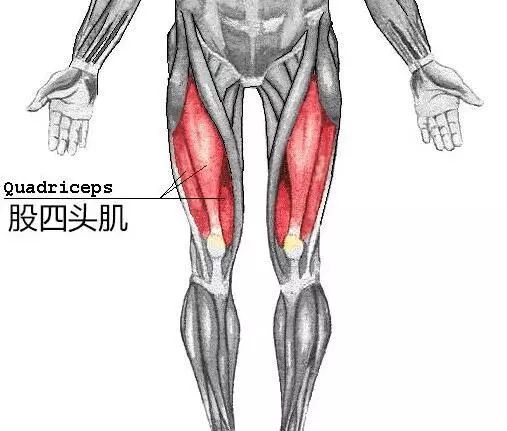

股四头肌

很多引起膝关节疼痛的疾病确实是由于关节过度磨损造成的,但医生强调的锻炼是指非负重条件下的肌肉锻炼,尤其是股四头肌的训练。股四头肌位于大腿前部。它是人体最大、最有力的肌肉。它由四部分组成。同时具有伸膝、屈髋的功能,对稳定膝关节有较强的作用。